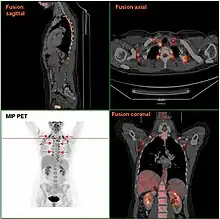

Chez l'adulte, la nécessité de ces adipocytes est discutable car ils ne sont plus indispensables après le 28e jour postnatal, même si la présence résiduelle de tissus adipeux est possible chez le nourrisson [18]. Le tissu adipeux brun peut être retrouvé chez l'adulte, de manière plus importante chez la femme[19]. Il tend à disparaître avec l'âge mais essentiellement chez l'homme, spécialement chez les sujets obèses[20]. La graisse brune peut parfois se développer chez l'adulte sur un mode tumoral bénin constituant alors un hibernome. Ce type de graisse peut être détecté grâce à la tomographie par émission de positons utilisant le fluorodésoxyglucose comme traceur[21].